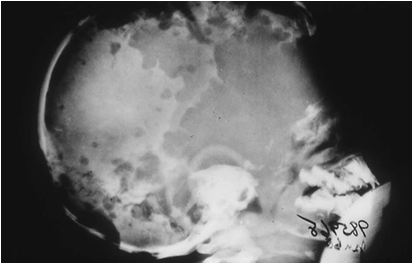

Radiological features:-